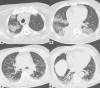

Results: According to RT-PCR results, 152 patients were COVID-19 negative (48%) and 162 were COVID-19 positive (52%). We found substantial agreement between RT-PCR results and CT findings (p < 0.000001), as well as an almost perfect agreement between the two readers. Mixed GGO and consolidation pattern with peripheral and bilateral distribution, multifocal or diffuse abnormalities localized in both upper lung and lower lung, in association with interlobular septal thickening, bronchial wall thickening and air bronchogram, showed higher frequency in COVID-positive patients. We also found a significant correlation between CT findings and patient's oxygenation status expressed by PaO2/FIO2 ratio.